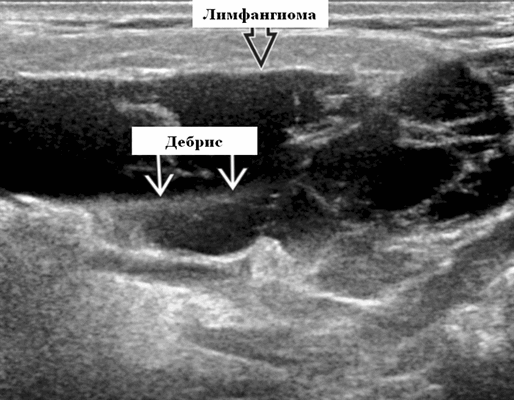

Результаты ультразвукового исследования. Серошкальное УЗИ. Более крупные околоушные лимфангиомы могут быть обнаружены при пренатальном УЗИ. Чаще мультилокулярный, чем монокулярный. Кистозные пространства могут быть округлыми или вкраплениями. Поверхностные поражения сжимаются ультразвуковым датчиком. Внешний вид зависит от того, было ли ранее кровотечение / инфекция. Негеморрагический / неинфицированный лимфаангимоы выглядят на УЗИ как однокамерные или многокамерные (чаще) анэхогенные сжимаемые кисты с тонкими стенками и промежуточными септами. Несмотря на большие размеры, существенного масс эффекта нет. Тонкие незаметные стенки с задним акустическим усилением. Цветной допплер: в области поражения нет кровеносных сосудов. Геморрагический / инфицированный тип лимфатической мальформации. Однокамерные или многокамерные гетерогенные кисты с неровными стенками, внутренним дебрисом. Несжимаемые датчиком и гипоэхогенные полости с толстыми стенками и перегородками. Уровни жидкости-жидкости из-за осаждения и разделения жидкостей предполагают предшествующее кровотечение. Цветной допплер: при заражении; васкуляризация может быть видна в стенках, перегородках и прилегающих мягких тканях